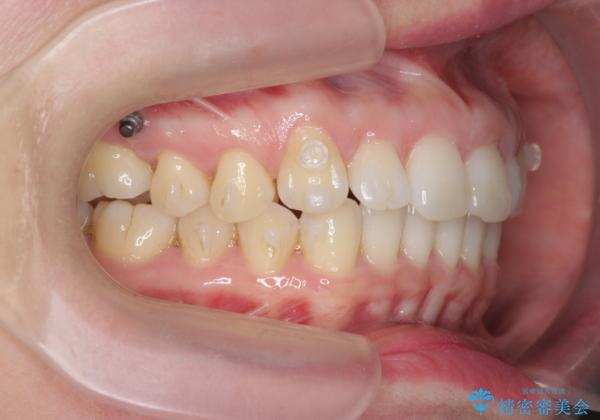

- 前歯の突出感、出っ歯の治療を希望され来院されました。

インビザラインを用いた治療計画を立て、しっかりと出っ歯を治すためにマイクロインプラントを併用します。

マイクロインプラントを併用することでしっかりとマウスピース全体を後方へ引き、前歯の突出感を改善することができました。